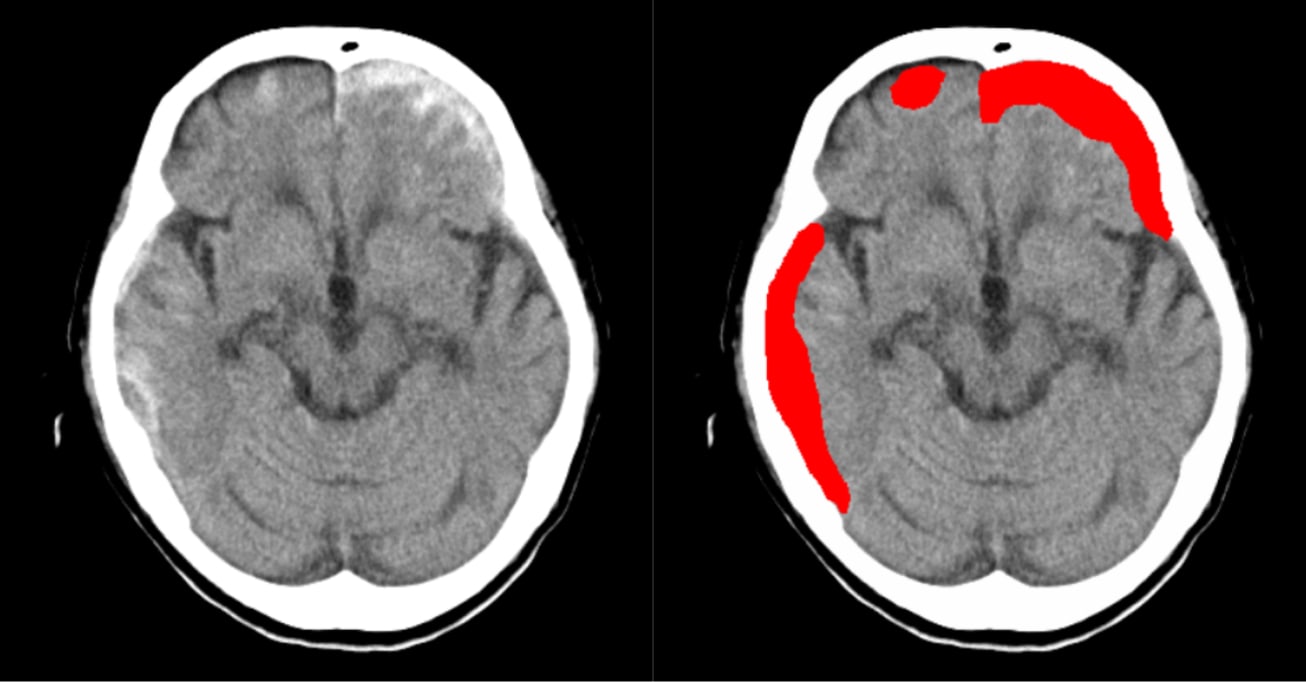

高吸収/低吸収領域及び、

組織構造・境界の不明瞭化領域の抽出・表示

- CT画像情報から頭蓋内の高吸収・低吸収領域を抽出

頭部単純CTの画像情報から頭蓋内の高吸収・低吸収領域を抽出し強調表示をします

- 頭部単純CTの画像情報から頭蓋内の高吸収・低吸収領域を抽出し強調表示をします

- 頭蓋内で前後のスライス及び同一スライス内の左右で比較して組織構造もしくは組織境界の不明瞭化が見られる領域を表示します

- 抽出領域がセグメンテーション表示されることで視覚的な確認が可能です